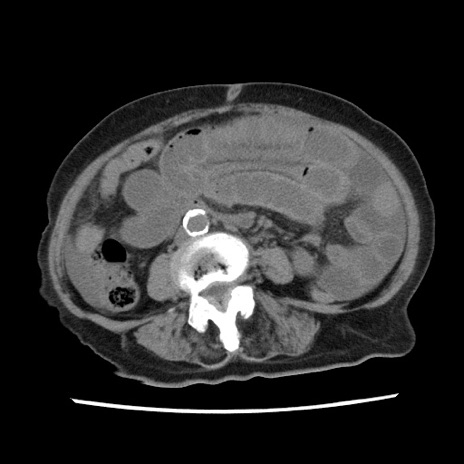

症例1(横断像)

【症例】80歳代女性

【主訴】腹痛

【現病歴】8時間前から腹痛あり来院。

【既往歴】糖尿病、脂質異常症、子宮体癌にて子宮全摘術

【身体所見】意識清明・会話良好だが腹痛で苦悶様、全腹部にわたって反跳痛と圧痛あり

【データ】WBC 13600、CRP 0.14、LDH 224、CK 90